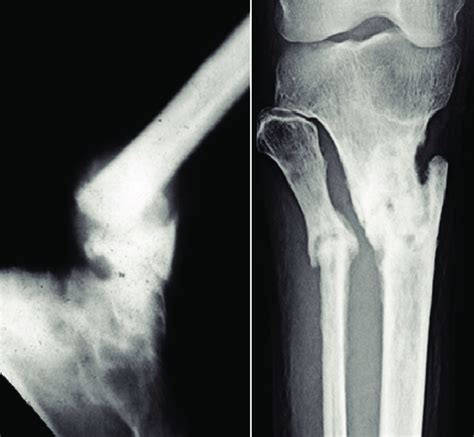

When we talk about pseudarthrosis , it’s not always a one-size-fits-all situation, guys. Doctors often categorize it to better understand the problem and plan treatment. One common way to classify it is based on its appearance and biological activity. We’ve got hypertrophic pseudarthrosis , and then there’s atrophic pseudarthrosis . Let’s break these down. Hypertrophic pseudarthrosis is often considered the more ‘hopeful’ type, if you can call it that. Here, the body is still trying! You’ll see evidence of attempted healing, like enlarged ends of the bone with what we call ‘elephant ear’ formations or ‘spikes’ (osteophytes) at the fracture site. There’s a lot of callus formation, but it’s disorganized and insufficient to bridge the gap. Think of it as a construction site where there’s a lot of activity, but the building materials just aren’t connecting properly. This type usually indicates a mechanical instability problem – the fracture just hasn’t been held still enough. On the other hand, atrophic pseudarthrosis is the more concerning one. In this scenario, the ends of the bone are often atrophied (shrunken, wasted away) and smooth , with no signs of attempted healing or callus formation. It’s like the body has given up on trying to fix it. The fracture gap might be wide, and the bone ends look dead or non-viable. This can happen due to poor blood supply, infection, or significant bone loss at the fracture site. Atrophic pseudarthrosis is generally harder to treat because there’s less biological activity to work with. Sometimes, you’ll also hear about oligotrophic pseudarthrosis , which is a less common term, often considered an intermediate form between hypertrophic and atrophic, showing minimal signs of healing. Understanding these distinctions helps doctors figure out why the bone isn’t healing and what the best approach will be.

Spotting pseudarthrosis isn’t always straightforward, but doctors have some pretty solid tools in their arsenal to figure out if you’ve got a non-union going on. The first thing they’ll do is talk to you – get a detailed medical history . They’ll ask about the original injury, how it was treated, if you’ve had any pain or instability, and if you’ve noticed any changes. This is super crucial information, guys! Then comes the physical examination . The doctor will carefully feel the area of the old fracture, check for tenderness, swelling, and most importantly, assess the range of motion and stability. They might try to move the limb gently to see if there’s abnormal movement at the fracture site, which is a big red flag. But the real heavy hitters in diagnosis are the imaging studies. X-rays are usually the first line of defense. They’re great for showing the bone structure, looking for a clear gap between the bone ends, the absence of a solid bone bridge (callus), and potentially signs of instability or bone changes. However, sometimes X-rays aren’t enough, especially if there’s a lot of hardware from previous surgery or if the problem is subtle. That’s where other imaging comes in. CT scans (Computed Tomography) provide much more detailed cross-sectional images of the bone. They’re excellent for visualizing the fracture gap, the bone ends, and the surrounding structures, giving a clearer picture of whether healing is occurring. MRI scans (Magnetic Resonance Imaging) are particularly good at showing soft tissues, like muscles and ligaments, but they can also provide valuable information about the bone marrow and any potential inflammation or infection at the site. Sometimes, if infection is suspected, a bone scan or even a biopsy (taking a small sample of bone tissue) might be necessary to confirm it. Essentially, diagnosis is a detective game, piecing together your story, physical findings, and detailed imaging to confirm that the bone has indeed failed to heal and determine the most likely cause.